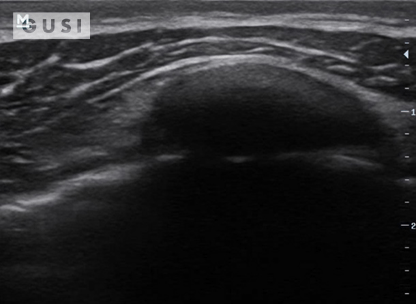

During the 2018 World Taekwondo Junior Championships in Hammamet, Tunisia, a 17-year-old male junior Taekwondo athlete took a fall, landing on his right shoulder. He exhibited a markedly limited range of motion in the affected shoulder and experienced intense pain, leading to suspicions of a dislocation.

|

|

|

|

|

A pre-reduction ultrasound (A) of the right shoulder showed a pronounced gap between the humeral head (indicated by a solid arrow) and the glenoid (marked by an open arrow), suggesting an anterior dislocation. Following a shoulder reduction procedure, a post-reduction ultrasound (B) verified the successful realignment of the glenohumeral joint (solid arrow pointing to the humeral head and open arrow to the glenoid).

After the procedure, the athlete displayed a considerably improved range of motion in his right shoulder and his pain levels diminished significantly.